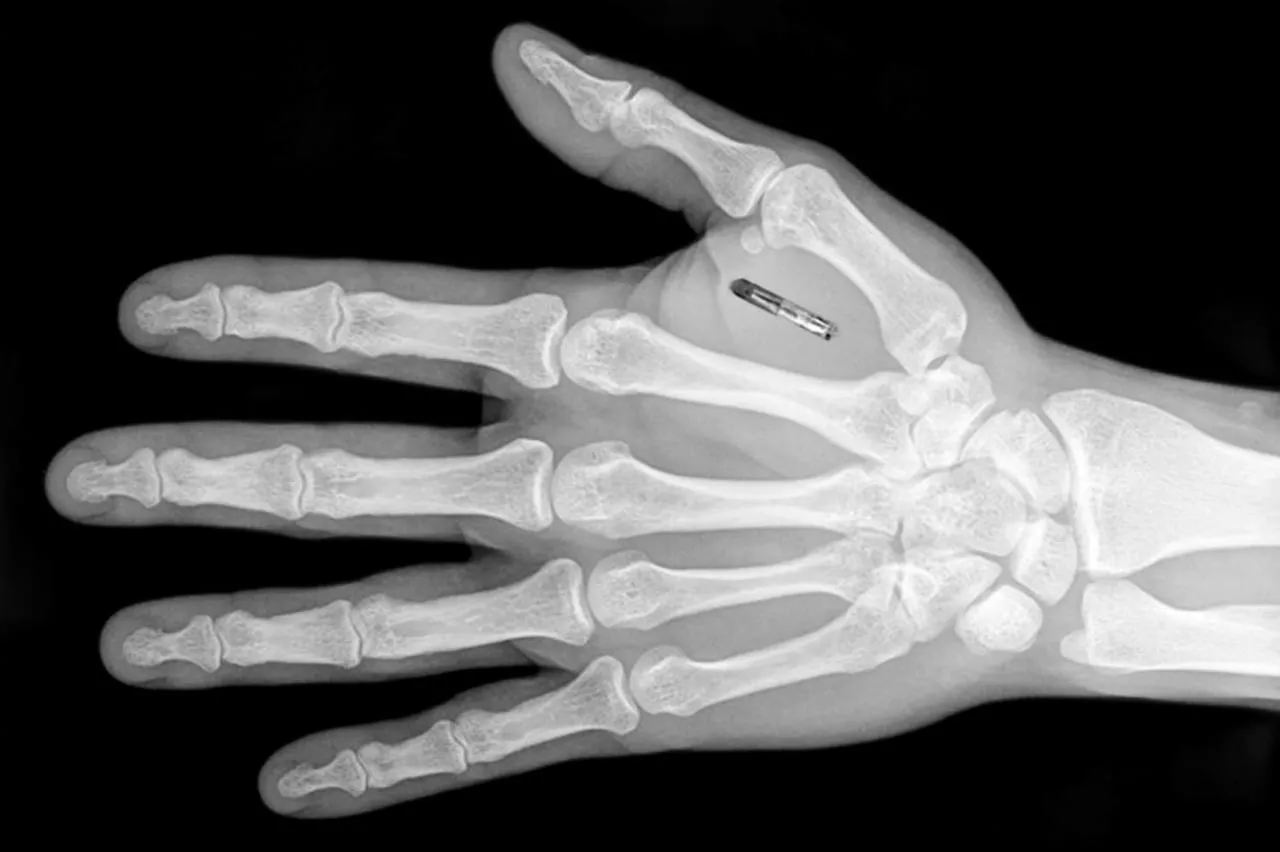

The RFID (radio-frequency identification) chips are about the size of a grain of rice and are inserted by a tattooist between the thumb and index finger. The technology have been offered to the 400 people at the Epicenter office block in Sweden, with some more willing than others about having the device implant.